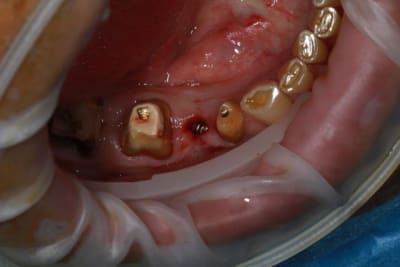

Nouveau patient, pose d'un implant il y a 2 mois....échec sans raisons particulières, douleurs et dépose.

Ce matin repose d'un nouvel implant et comme je ne veux pas prendre de risque, et que les dents adjacentes doivent être couronnées, je pose un bridge en emax press, mais scellé au ciment provisoire...

alors là pas du tout, le patient vient me voir pour des implants, donc je fais une étude du cas absence des molaires supérieures, couronnes mandibulaires très ancienne 45 racine cassée, 44 dévitalisée mais passablement déchaussée, donc avulsion de 45 et pose d'un implant avant de refaire les couronnes 46/47 et l'ensemble.

Échec implantaire, et oui ça arrive, même dans un cas paraissant simple.

Dépose gratuite bien sur et repose gratuite aussi, le bridge n'est pas facturé non plus, il le sera sous forme de 2 couronnes que cette fois ci l'implant fonctionne ce que j’espère, ou laissé en bridge si l'implant devait être retiré.